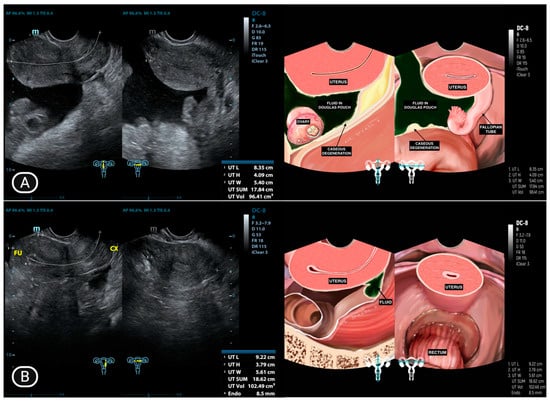

| 3 | IO (31) * | Caseous degeneration on the surface | Adhesion complex | Normal | Adhesion complex | Normal | (−) | Caseous degeneration on the surface of rectosigmoid colon and small bowel |

| 4 | SMK (29) * | Caseous degeneration on the surface. Complex fluid behind uterus | Normal | Not visualized | Adhesion complex with left fallopian tube | Hydrosalpinx | Complex fluid in cavum of Douglas with caseous degeneration | Caseous degeneration on the surface of rectosigmoid colon |